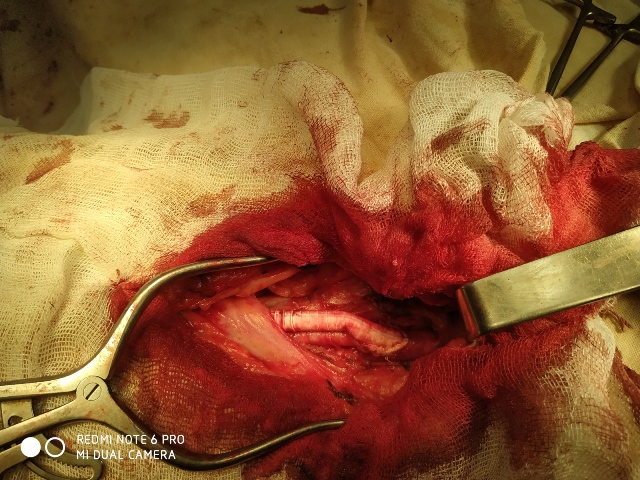

Хирургическая помощь

В ГУ «ЛРКБ» ЛНР ОСХ сотрудниками кафедры госпитальной хирургии и онкологии и врачами ГУ «ЛРКБ» ЛНР ежедневно оказывается специализированная хирургическая помощь больным с атеросклерозом магистральных артерий нижних конечностей.

Больному было сделано аорто–бифеморальное шунтирование и протезно–подколенное шунтирование справа. (Операционная бригада: Лящук А.В., Нижельский В.Е., Редин Д.Е.; Анестезиолог: Никитич А.В.)

03.03.2020 - производилась плановое оперативное лечение пациенту с окклюзией левой поверхностной бедренной артерии.